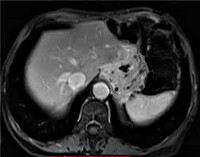

Более подробную информацию о состоянии близлежащих органов и лимфатических узлов при рецидиве рака желудка получают при помощи КТ органов брюшной полости. Иногда с этой же целью проводят лапароскопию, позволяющую оценить состояние передней поверхности желудка, нижней и передневерхней поверхности печени, яичников и селезенки, обнаружить асцит и канцероматоз брюшины. Для определения уровня анемии пациентам с рецидивом рака желудка назначают общий анализ крови, для оценки функций печени и почек выполняют биохимический анализ крови. Окончательный диагноз выставляют после морфологического исследования материала, взятого во время гастроскопии.